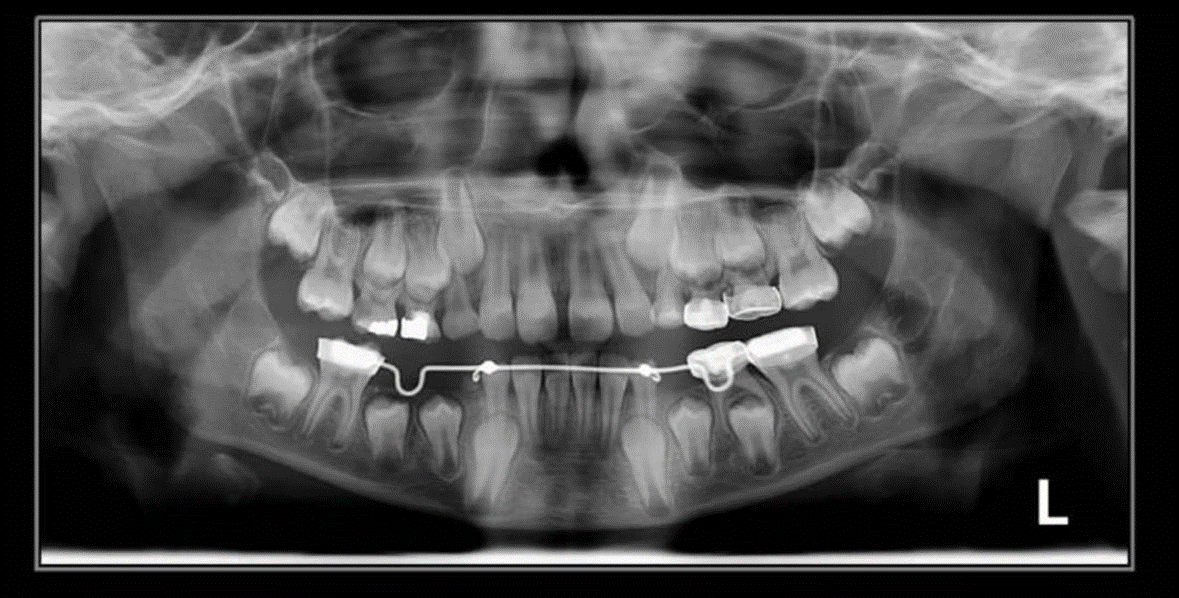

3. How old is the patient with the following X ray?